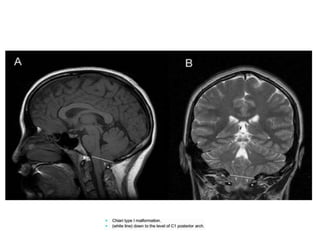

Arnold-Chiari Malformation

• Type 1- m/c -caudal displacement of peglike cerebellar tonsils

below the level of the foramen magnum, -congenital tonsillar

herniation, tonsillar ectopia, or tonsillar descent.

• Syringomyelia in 50 to 70%.